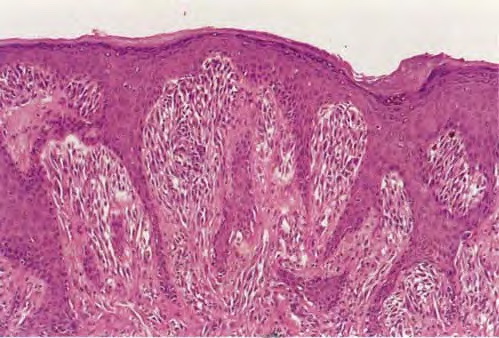

Spitz naevus (juvenile melanoma) = وحمة سبيتز _الميلانوم الفتوي